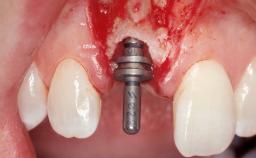

Late Placement of an Implant in a Maxillary Left Central Incisor Site

A 36-year-old female patient was referred for the replacement of the upper left central incisor (tooth 21), which had fractured. Although the tooth had been asymptomatic for many years, the crown began to loosen, at which time she presented to her dentist for an assessment. Teeth 21 and 22 had both been endodontically treated many years previously. She was a healthy individual and a non-smoker.

On examination, the patient had a low lip line and only displayed the coronal half of the anterior teeth when smiling.

The crown of tooth 21 was splinted to the adjacent teeth with composite resin, and the gingiva was inflamed.